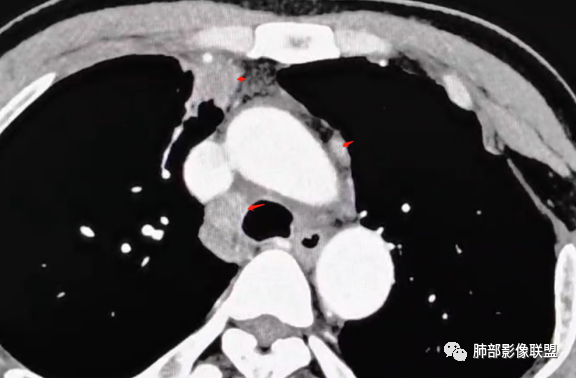

Coke with ice分析

1、补充一点点征象,欢迎拍砖。

病变诊断炎性是比较明确的。老师们说了很多依据,我再加几个征象

1

红箭-支气管分叉间条形高密度

2

这个脂肪间隙很模糊。

3

这里也是。还有血管增粗。

4

增大淋巴结

很多增大的淋巴结,强化方式一致均匀,

未见明确坏死,融合不明显,没有明确的分布优势。

5

这里是软组织密度,纵隔内突入

我觉得这里可以怀疑是栽桩。

肝脏病变明确,是轻度强化,延迟强化特点,边缘模糊,有轻微的包膜挛缩。

6

是不是有气管壁的增厚呢?

反复看薄层视频,我拿不准有没有支气管膜部受累的情况,但是这些支气管管壁增厚感觉有点可疑。

7

平扫。这种淋巴结密度偏高,还是挺多这种略高密度淋巴结的

2、思路,支气管分叉处的这种锐角突起,邻近胸膜脂肪间隙密度模糊,加上老师们标记的其他征象,猜炎性在前